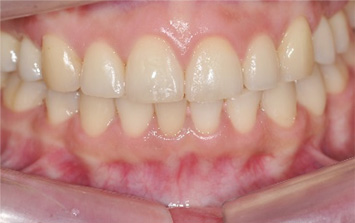

앞니가 정상적으로 물이지 않아 심미적인 문제와 음식물을 섭취할 때 상당한 불편함을 느껴 내원한 환자.

고운미소에서는 교정용 와이어와 미니스크류를 사용하여 치열의 수직적인 문제를 개선하는 치아교정을 시행하였습니다.

앞니가 서로 물리게 되어 음식물을 씹는 저작 문제와 심미적인 문제가 해결되어 교정을 완료하였습니다.